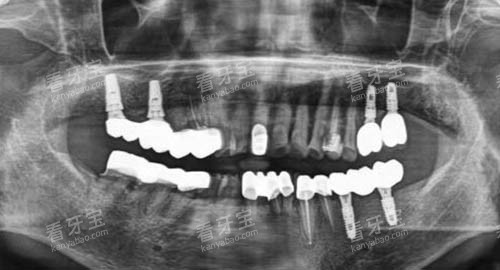

此外,张月鹏口腔还拥有智能化口腔全景机、口腔 CT、超声洁牙机等靠前设备,能够为患者提供超全、较准的口腔检查和诊断,为治疗方案的制定提供科学依据。